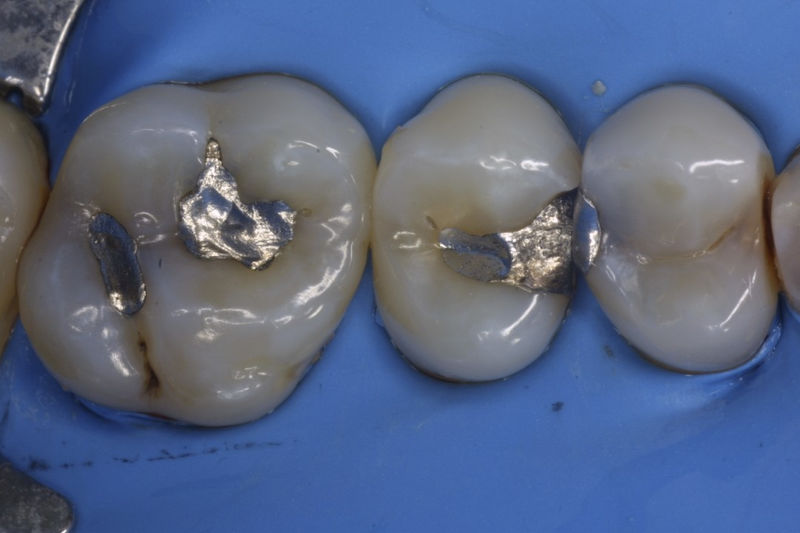

Restauraciones fabricadas en el laboratorio con materiales estéticos, los cuales cubren de manera parcial dientes posteriores. Se utilizan primariamente para restaurar dientes con caries, fracturas y/o defectos amplios. Para poder enviar el caso al laboratorio se toman impresiones utilizando materiales de impresión o técnicas modernas digitales.

Restauraciones fabricadas en el laboratorio con materiales estéticos, los cuales cubren de manera total dientes anteriores y posteriores. Se utilizan primariamente para restaurar dientes con caries, fracturas y/o defectos amplios, así como soportes de puentes. Para poder enviar el caso al laboratorio se toman impresiones utilizando materiales de impresión o técnicas modernas digitales.